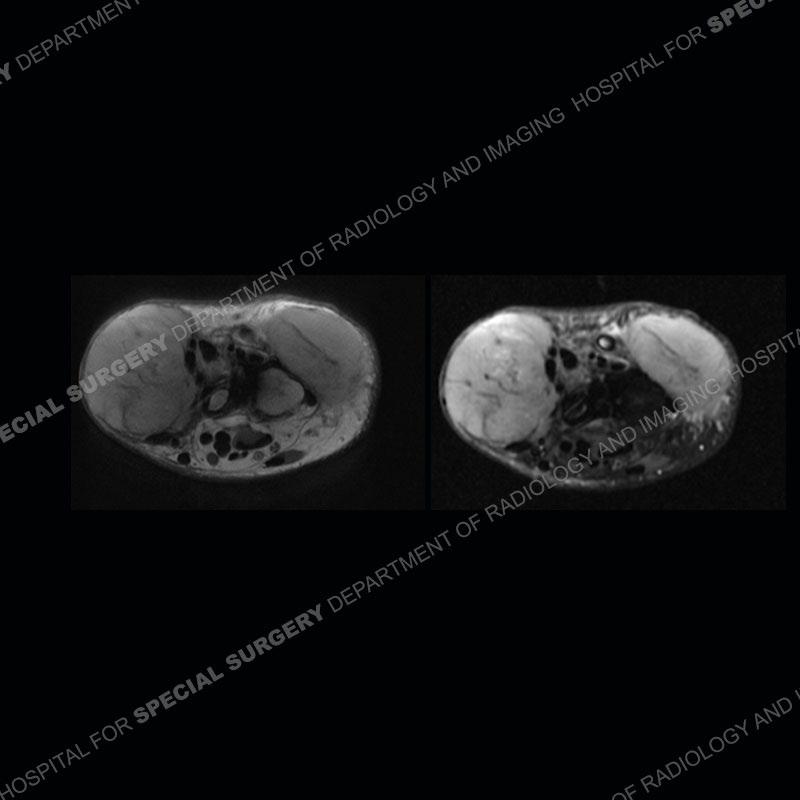

The original MRI shows a mass of the distal radius which extends to the end of the bone. There is expansion of the distal radius with the mass penetrating through the bone particularly slightly into the dorsal soft tissue. There is a suggestion of subtle fluid levels of the mass on the T2 axial image. Resection was performed with a fibular autograft utilized for wrist fusion. Subsequent imaging demonstrates multiple soft tissue masses with faint, peripheral calcification. On MRI, the masses are similar in appearance to the original mass of the distal radius.

Diagnosis: Soft Tissue Recurrence of Giant Cell Tumor of Bone

Giant cell tumor of bone is a fairly aggressive although most frequently benign process (malignancy can only be assessed via pathology). The preoperative study is typical with an end of the bone lesion in a relatively young patient with expansion of the bone and somewhat aggressive characteristics. Treatment can be done by curettage and bone grafting/packing or as in this case with resection and limb reconstruction. One of the rare postoperative situations is soft tissue recurrence. Although not completely understood, it is thought to be related to soft tissue contamination at the time of surgery to treat the lesion. The very low occurrence of this process makes conclusions somewhat limited in their value; however, the soft tissue recurrence is perhaps more prominent when the lesion already extends into the soft tissue. Additionally, treatment with curettage as compared to resection does appear to have an increased risk of soft tissue recurrence.

The soft tissue masses of recurrence of giant cell tumor of bone often do have a peripheral, thin rim of calcification or less commonly, dense, central calcification (lesions without calcification still tend to predominate). This is particularly interesting given the extremely uncommon scenario of mineralization of a native giant cell tumor of bone. Postoperative radiographs showing soft tissue mineralization in these patients should raise suspicion for soft tissue recurrence. This patient was originally treated at an outside, international center and came to our institution for the treatment of his soft tissue masses. The patient is currently undergoing denosumab treatment to help decrease the size of the masses and mineralize the masses to aid in making their resection easier.